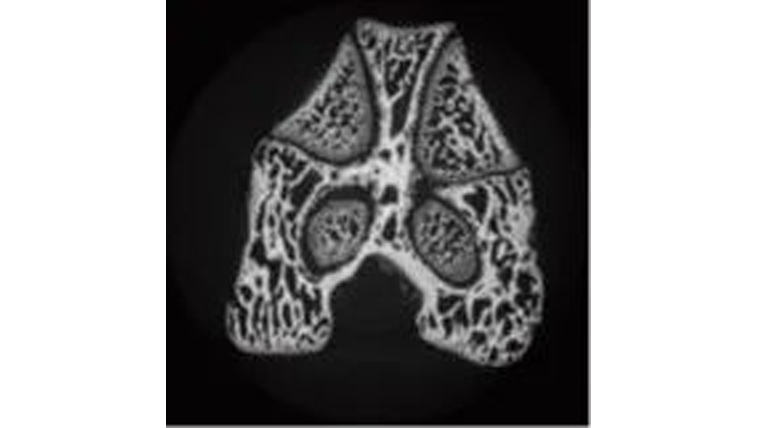

图4为骨骺的横断面图像,图5为骺端和干骺端横断面图像,图6为干骺端的横断面图像。在干骺端横断面上,圆形骨区为皮质骨,内部网状区为骨小梁。使用inspeXioSMX-100CT进行锥束扫描,一次即可获得区域内所有的横断面图像,还可以连续进行图像观察。

图4骨骺的CT图像

图5骺端和干骺端的CT图像

图6 干骺端CT图像